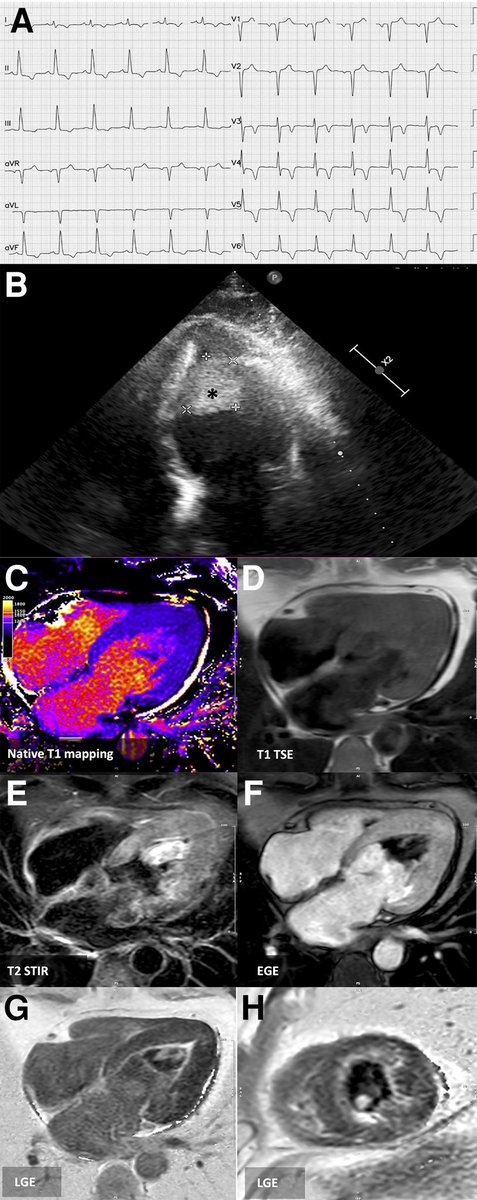

#EHJCaseReports poll 1/2 66/M p/w SOB on exertion. ECG as shown (2/2). Nil other significant past medical hx of note. What would you expect to find on #whyCMR? https://t.co/RLucrYxe8t @TJ_Yeo @aayshacader @ANazmiCalik @Phiso_de @ESC_Journals @escardio @ESC_Lavinia

@TJ_Yeo @aayshacader @ANazmiCalik @Phiso_de @ESC_Journals @escardio @ESC_Lavinia #EHJCaseReports poll answer The ECG is consistent with HCM, so all findings are likely (LVH, LV cavity obliteration & LGE) We have a double feature today at @ESC_Journals for this case: https://t.co/RLucrYwGiV Share your cases w us: https://t.co/9qUo9LSsdw

Apical HCM, endomyocardial fibrosis & hypereosinophilic syndrome all in 1 https://t.co/By1yMWgH7m #EHJCaseReports @aayshacader @ANazmiCalik @TJ_Yeo @Phiso_de @EHJCREiC #CardioX #echofirst #whyCMR